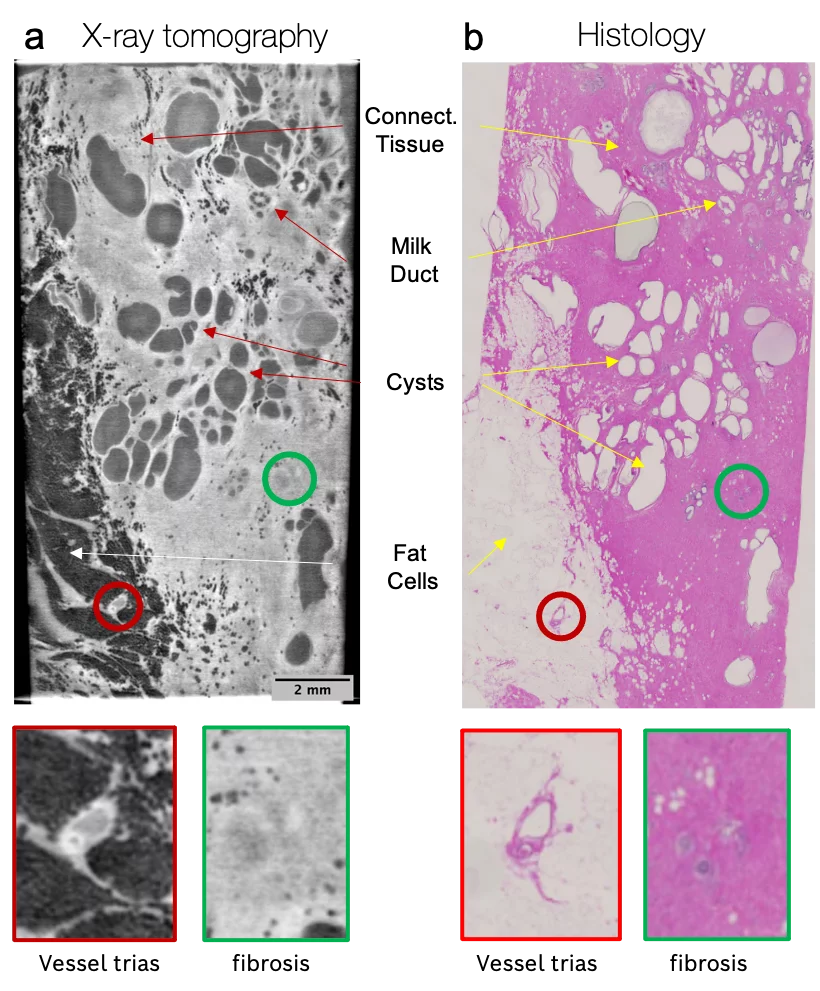

In our team, a prototype of the new X-ray uCT setup was assembled. Based on the grating interferometry, the system provides high spatial resolution (<10 µm) and field of view (up to 2.0 cm). Therefore, the three-dimensional information obtained from X-ray phase-contrast microtomography nicely corresponds to the images obtained by conventional histological techniques.